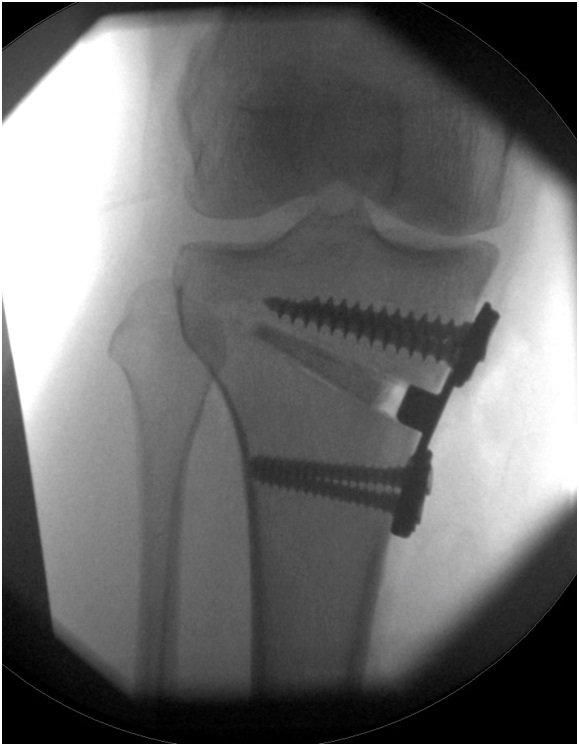

The operation is performed under a general anaesthetic. An incision is made over the bone that is to be realigned. Then, a cut is made in the bone almost all the way through, leaving intact a small amount of bone that acts as a hinge. The bone is then carefully hinged open the appropriate amount and held in place by a plate and screws which are fixed into the bone.

The operation straightens the leg and may even overcorrect it so that a bow-legged knee ends up being slightly knock-kneed and vice versa. This reduces the force going through the worn out part of the knee and loads the normal part of the knee.